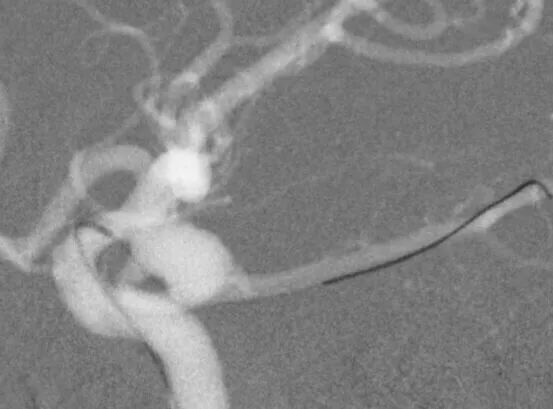

左侧后交通动脉瘤,胚胎型大脑后动脉

3D

局部观,宽颈,涉及颈内动脉和后交通动脉

椎动脉造影见左侧大脑后动脉P1段很细